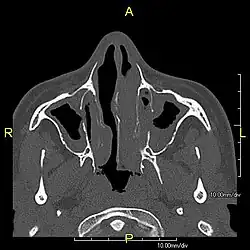

| Complications | Chronic recurrent respiratory infections, including sinusitis, bronchitis, pneumonia, and otitis media.[2] |

Around 80% of people with primary ciliary dyskinesia experience respiratory problems beginning within a day of birth. Many have a collapsed lobe of the lung and blood oxygen low enough to require treatment with supplemental oxygen.[1] Within the first few months of life, most develop a chronic mucus-producing cough and runny nose.[1] The main consequence of impaired ciliary function is reduced or absent mucus clearance from the lungs, and susceptibility to chronic recurrent respiratory infections, including sinusitis, bronchitis, pneumonia, and otitis media. Progressive damage to the respiratory system is common, including progressive bronchiectasis beginning in early childhood, and sinus disease (sometimes becoming severe in adults). However, diagnosis is often missed early in life despite the characteristic signs and symptoms.[2] In males, immotility of sperm can lead to infertility, although conception remains possible through the use of in vitro fertilization, there also are reported cases where sperm were able to move.[8] Trials have also shown that there is a marked reduction in fertility in females with Kartagener's syndrome due to dysfunction of the oviductal cilia.[9]

Diagnosis

Several diagnostic tests for this condition have been proposed.[5] These include nasal nitric oxide levels as a screening test, light microscopy of biopsies for ciliary beat pattern and frequency and electron microscopic examination of dynein arms, as the definite diagnosis method. Genetic testing has also been proposed but this is difficult given that there are multiple genes involved.[6]